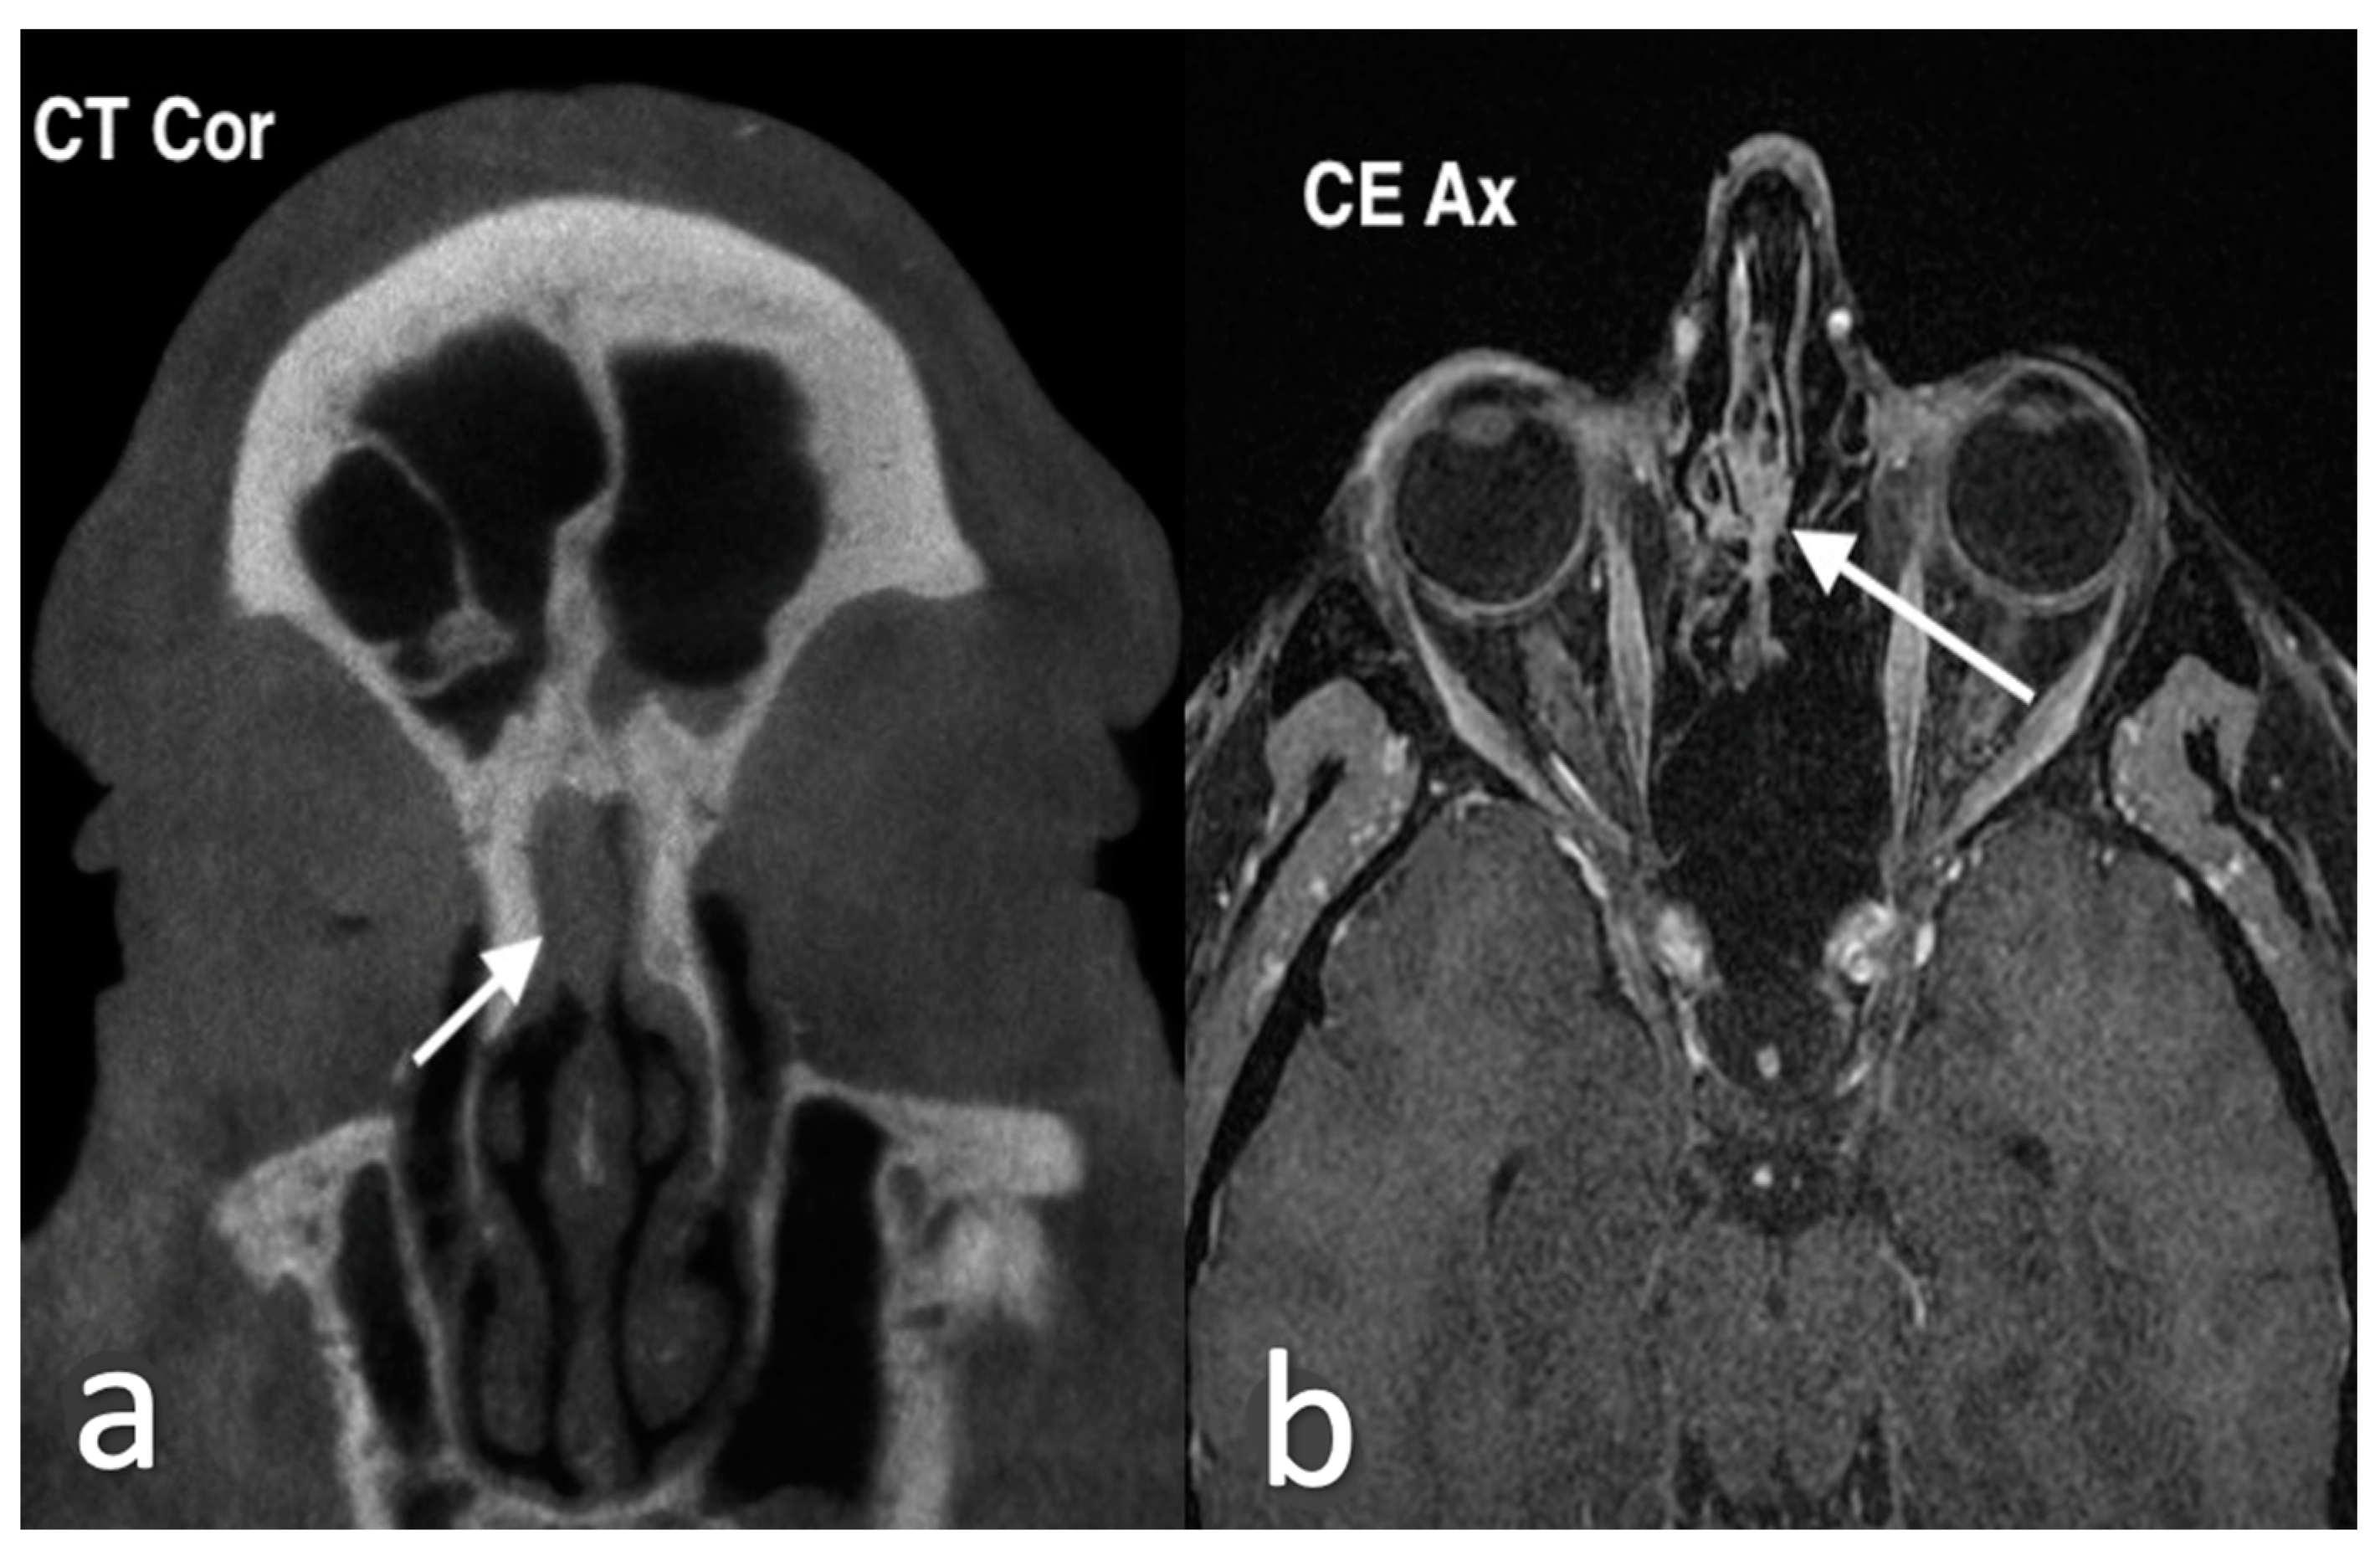

3.1.1. Septal Mucocele